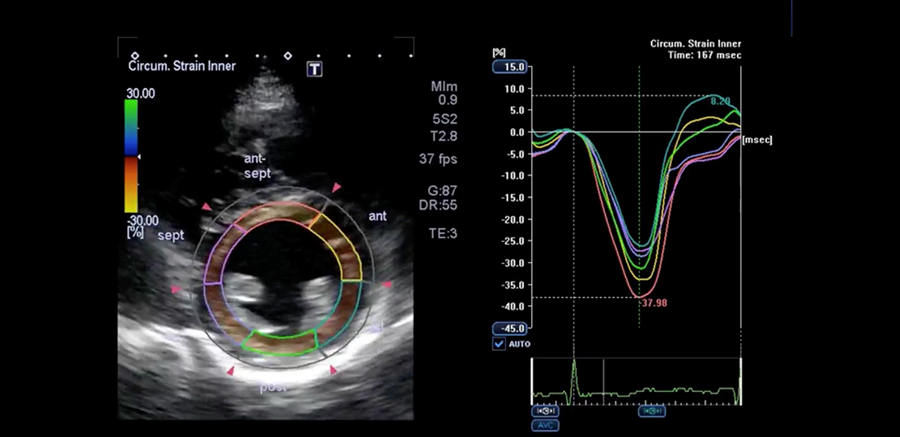

- This result is displayed on a linear graph as percent change over time (x-axis is time and y-axis is percent strain with green hashed vertical line representing aortic valve closure) and quantifies myocardial deformation.

- Defined abnormal strain pattern when all of the wall segments did not form a nearly single uniform line

Normal Parasternal Short Axis with Speckle Tracking

Abnormal Parasternal Short Axis with Speckle Tracking

Images provided courtesy of Dr. Lindsay Reardon